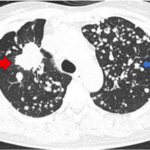

CASE LÂM SÀNG Điều trị bệnh nhân mắc đồng thời hai loại ung thư: Ung thư phổi và ung thư tuyến tiền liệt

CASE LÂM SÀNG Điều trị bệnh nhân mắc đồng thời hai loại ung thư: Ung thư phổi và ung thư...

Case lâm sàng: Điều trị miễn dịch kết hợp thuốc kháng tăng sinh mạch cho bệnh nhân ung thư biểu mô tế bào gan tại trung tâm y học hạt nhân và ung bướu – BV Bạch Mai

Case lâm sàng: Điều trị miễn dịch kết hợp thuốc kháng tăng sinh mạch cho bệnh nhân ung thư biểu...